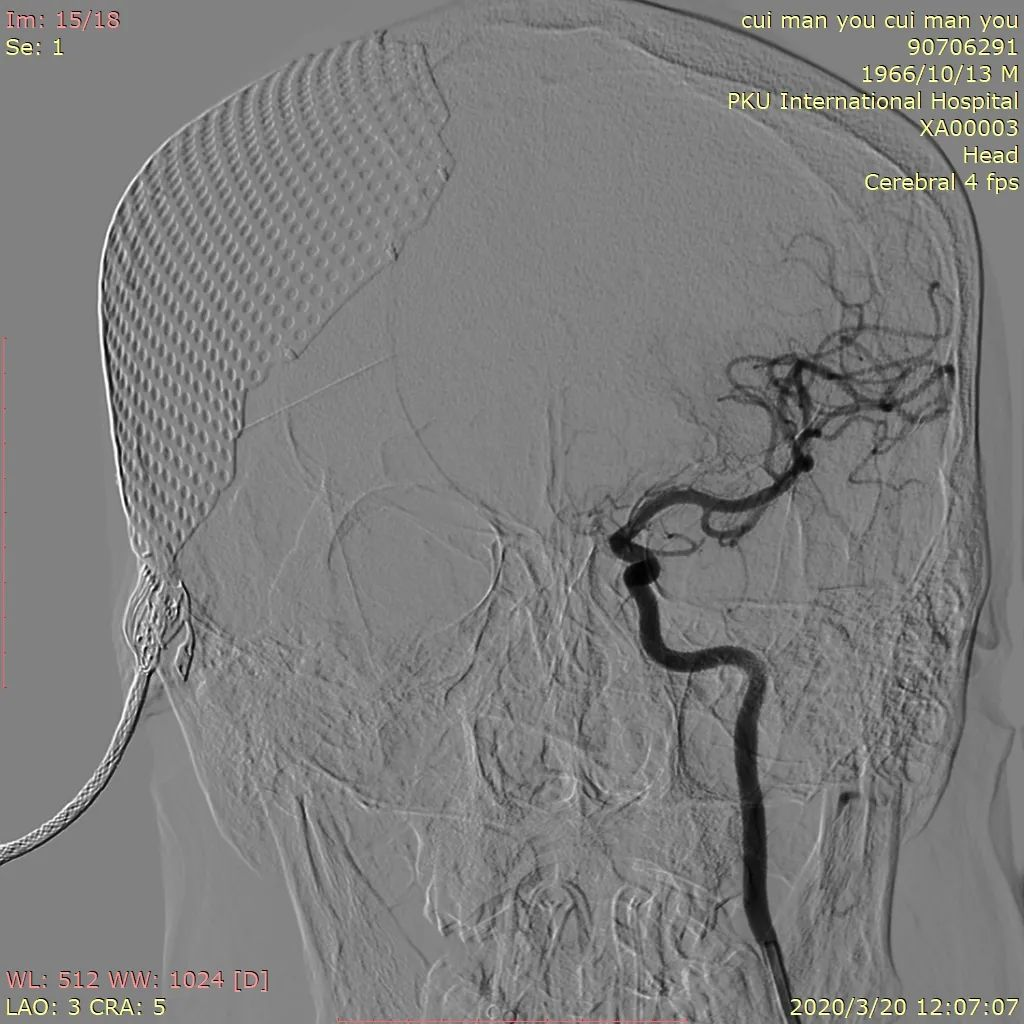

图2 左侧颈内动脉压颈造影见左侧A1段缺如

图4 Headway21及Headway17直头微导管到位,第一枚弹簧圈成篮